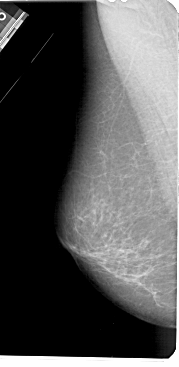

A_1433_1.LEFT_MLO

LEFT_MLO LINES 5491 PIXELS_PER_LINE 2671 BITS_PER_PIXEL 12 RESOLUTION 43.5 NON_OVERLAY